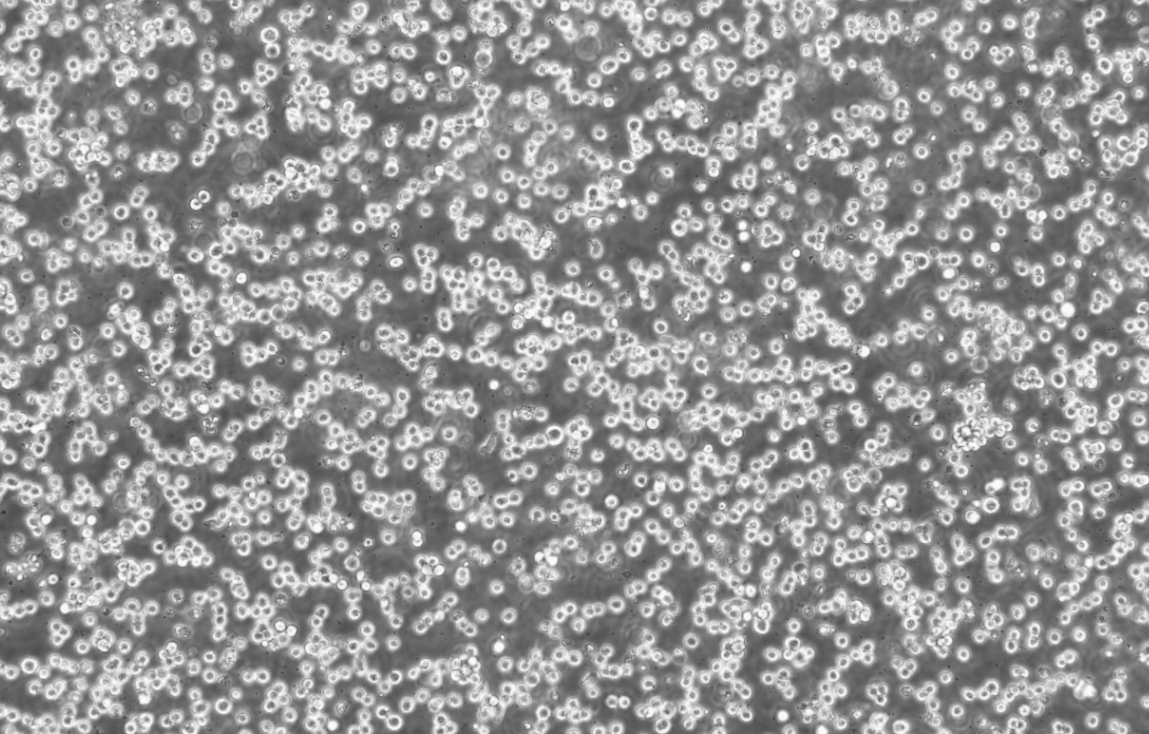

形態 |

圓形 |

生長特征 |

懸浮生長 |